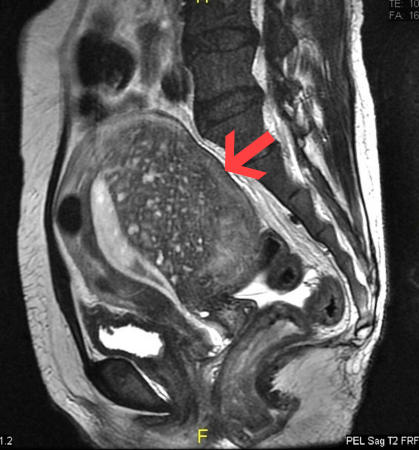

Adenomyosis

Sagittal MRI of a woman's pelvis showing a uterus with adenomyosis in the posterior wall. Gross enlargement of the posterior wall is noted, with many foci of hyperintensity

Case courtesy of Dr Varun Babu, Radiopaedia.org. From the case rID: 43504; reproduced under the Creative Commons CC BY-SA 4.0 license (https://creativecommons.org/licenses/by-sa/4.0/)